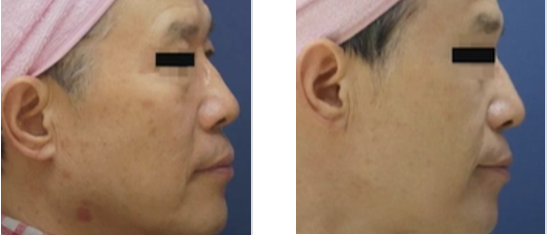

탄력 개선

탄력 개선